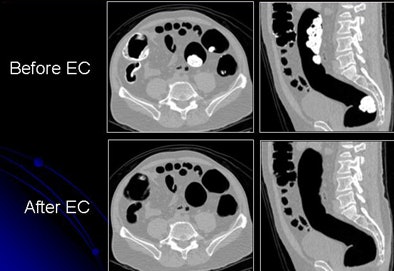

| Images show CTC data before and after electronic cleansing. All images courtesy of Hiro Yoshida, Ph.D. |